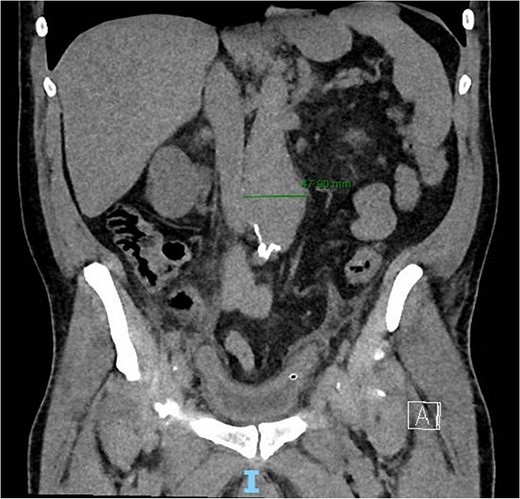

A 56-year-old male with no reported past medical history and a 70 pack year smoking history presented with a chief complaint of lower abdominal pain and body aches. On presentation, the patients white blood cell count (WBC) was 39.6 and procalcitonin was 43.4. Blood cultures were drawn and demonstrated P. mirabilis bacteremia. Computed tomography (CT) abdomen/pelvis was performed as well as ultrasound (US) of scrotum demonstrating a complex fluid collection within scrotal sac that was determined to be a scrotal wall abscess. The patient was started on a course of Unasyn and Urology promptly took him to the operating room (OR) for incision and drainage. Vascular surgery was consulted due to an incidental finding of an abdominal aortic aneurysm on CT measuring 4.7 × 4.6 cm (Figs 1 and 2). The patient was evaluated by the vascular surgery team following his urological procedure and denied any history of abdominal pain or back pain. Physical exam was largely unremarkable however the patient’s bilateral toes were noted to have blue discoloration with motor and sensation intact. Outpatient follow up with routine US scans for the AAA was recommended. Ankle brachial index (ABI) as well as an echocardiography was ordered to further work up the patient’s dusky toes. On Day 2 of hospitalization, ABIs returned showing severe peripheral vascular disease (PVD) and the echocardiography ruled out endocarditis. At this time an angiogram was planned to further the patient’s PVD workup however this was deferred as the patient remained septic with a WBC of 30. Over the course of the next few days the patient refused antibiotics and remained septic with a WBC in the 20s. At this time his toes quickly deteriorated from dusky to dry gangrene. On Day 8 of hospitalization the patient remained septic and was now complaining of new onset mid-abdominal pain. Emergent CT showed AAA was now 7.7 × 7.8 cm with periaortic fat stranding concerning for impending rupture (Figs 3 and 4). The patient was taken emergently to the OR for open repair. Upon visualization, the abdominal aortic aneurysm was clearly infected with signs of impending rupture on the left lateral wall and purulent material including infected thrombus. Tissue was cultured however showed no growth, likely due to the fact that the patient had been on antibiotic therapy for a week at this time. Reconstruction with an aorto-biiliac bypass using rifampin-soaked dacron graft was performed. A piece of omentum was mobilized over the graft and the retroperitoneum was closed over it. The abdomen was left open for a return to the OR for a second look which showed no concerns for bowel ischemia, worsening infection or bleeding. On post-op Day 5 the patient was extubated, off pressor support, and transferred to the floor. The patient’s postoperative course was unremarkable except for bilateral toes demarcating to dry gangrene.

Frontal CT angiography of the abdomen and pelvis demonstrating 7.75 cm AAA with fat stranding.

Axial CT angiography of the abdomen and pelvis demonstrating 7.7 cm AAA with fat stranding.